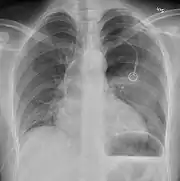

Chest X-ray

A plain chest radiograph, ideally with the X-ray beams being projected from the back (posteroanterior, or "PA"), and during maximal inspiration (holding one's breath), is the most appropriate first investigation.[30] It is not believed that routinely taking images during expiration would confer any benefit.[31] Still, they may be useful in the detection of a pneumothorax when clinical suspicion is high but yet an inspiratory radiograph appears normal.[32] Also, if the PA X-ray does not show a pneumothorax but there is a strong suspicion of one, lateral X-rays (with beams projecting from the side) may be performed, but this is not routine practice.[15][19]

Chest X-ray showing a pneumothorax on the right (left in the image), where the absence of lung markings indicates that there is free air inside the chest

Chest X-ray showing the features of pneumothorax on the left side of the person (right in image)

It is not unusual for the mediastinum (the structure between the lungs that contains the heart, great blood vessels, and large airways) to be shifted away from the affected lung due to the pressure differences. This is not equivalent to a tension pneumothorax, which is determined mainly by the constellation of symptoms, hypoxia, and shock.[13]

The size of the pneumothorax (i.e. the volume of air in the pleural space) can be determined with a reasonable degree of accuracy by measuring the distance between the chest wall and the lung. This is relevant to treatment, as smaller pneumothoraces may be managed differently. An air rim of 2 cm means that the pneumothorax occupies about 50% of the hemithorax.[15] British professional guidelines have traditionally stated that the measurement should be performed at the level of the hilum (where blood vessels and airways enter the lung) with 2 cm as the cutoff,[15] while American guidelines state that the measurement should be done at the apex (top) of the lung with 3 cm differentiating between a "small" and a "large" pneumothorax.[33] The latter method may overestimate the size of a pneumothorax if it is located mainly at the apex, which is a common occurrence.[15] The various methods correlate poorly but are the best easily available ways of estimating pneumothorax size.[15][19] CT scanning (see below) can provide a more accurate determination of the size of the pneumothorax, but its routine use in this setting is not recommended.[33]

Not all pneumothoraces are uniform; some only form a pocket of air in a particular place in the chest.[15] Small amounts of fluid may be noted on the chest X-ray (hydropneumothorax); this may be blood (hemopneumothorax).[13] In some cases, the only significant abnormality may be the "deep sulcus sign", in which the normally small space between the chest wall and the diaphragm appears enlarged due to the abnormal presence of fluid.[16]